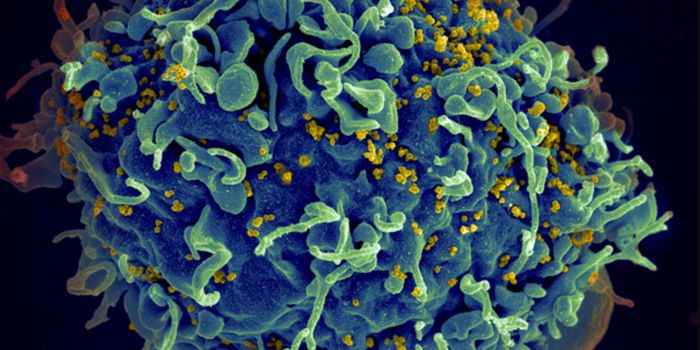

AUG 24, 2020ImmunologyOnce in the body, HIV tracks down T cells that bear the CD4 receptor. It attaches to these immune cells, fusing itself w ...

JUL 19, 2016CancerA decade-old technology to arm the immune system to fight cancer is now being adapted to fight HIV, one of the most pern ...

NOV 17, 2020ImmunologyLast year, around 1.7 million people became infected with HIV, with around half of these being women. Encouraging result ...

AUG 14, 2022ImmunologyFor the second time this year and only the fourth time ever, researchers have announced that a person has been cured of ...

MAY 23, 2024MicrobiologyWhen human immunodeficiency virus (HIV) emerged and was identified as the cause of acquired immunodeficiency syndrome (A ...